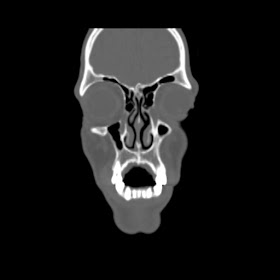

O/E images:

patient New hrct investigation images is:

know patient open his mouth after surgery :